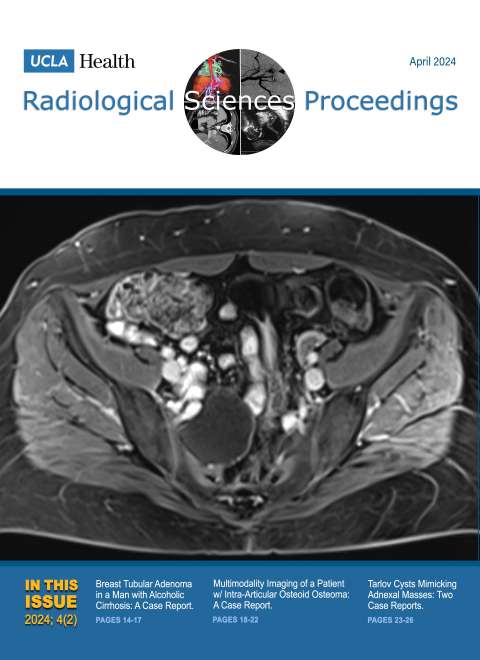

August 2024

Volume 4, Issue 3

- Differentiating Hemangioma and Secondary Angiosarcoma of the Breast: Two Case Reports

- Intraperitoneal Focal Fat Infarction of the Falciform Ligament: A Report of Two Cases

- Tilted Disc Syndrome with Bitemporal Hemianopia in a 67-Year-Old Woman with High Myopia and Mixed/Combined-Mechanism Glaucoma: A Report of a Rare Case